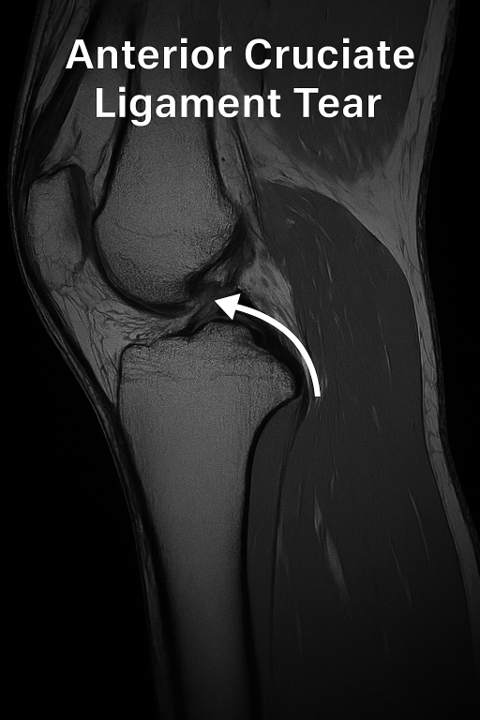

Image: ACL tear

Diagnosing an ACL Tear

Specific manual tests follow (e.g. Lachman test, anterior drawer test), and final diagnosis is confirmed using imaging techniques:

MRI (Magnetic Resonance Imaging) – allows visualization of soft tissues like ligaments, menisci, and cartilage

In most cases, an ACL injury is accompanied by damage to other structures like the menisci, collateral ligaments, and articular cartilage, which makes detailed imaging crucial.